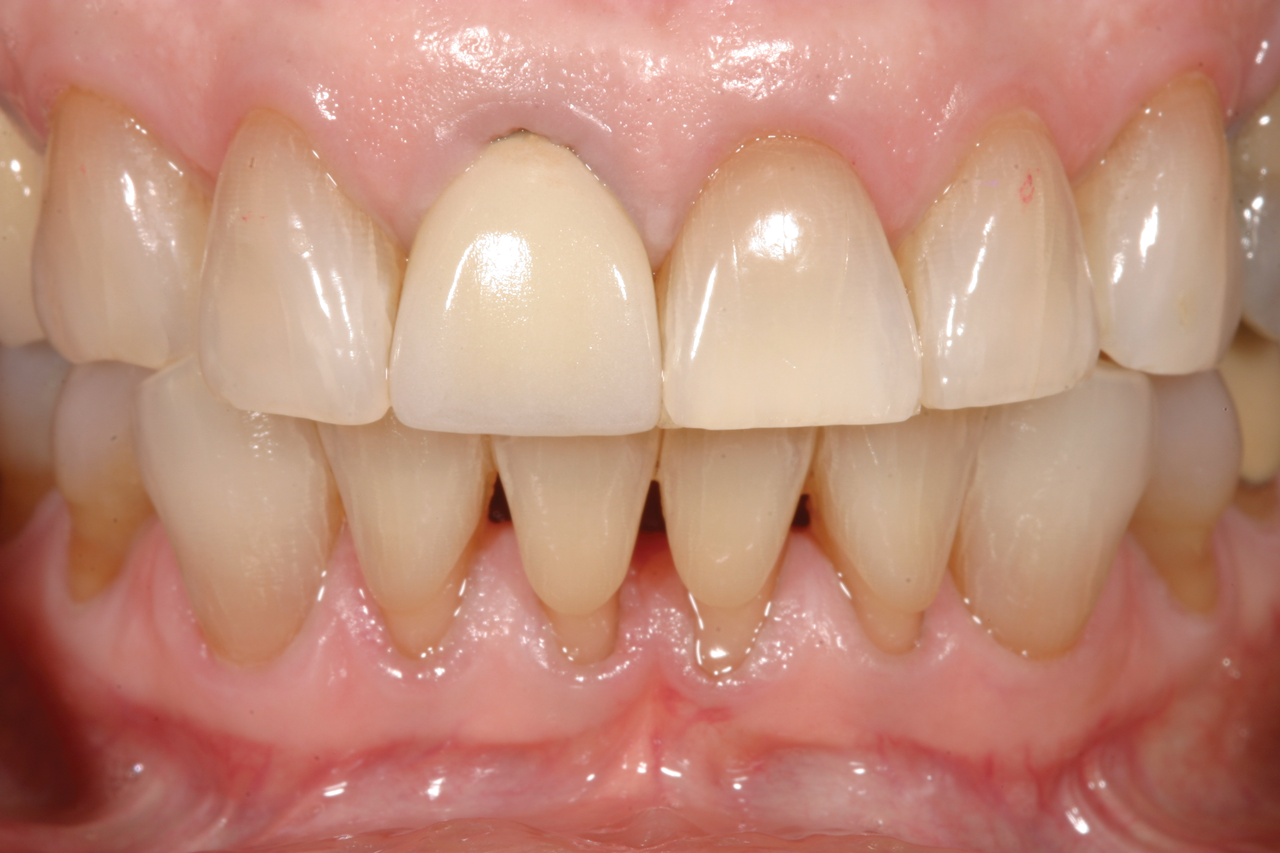

Fig 12. In a separate case, radiograph of implant No. 8 is shown. Previous endodontically treated tooth had fractured and the decision was made within a few months to extract and replace it with an implant. Bone was preserved to optimize the implant site.

Figure 12

Fig 13. Successful final restoration of implant No. 8. Had the clinician waited too long to extract the failing endodontically treated tooth No. 8, the result may have been compromised, especially if the patient had a high smile line.

Figure 13